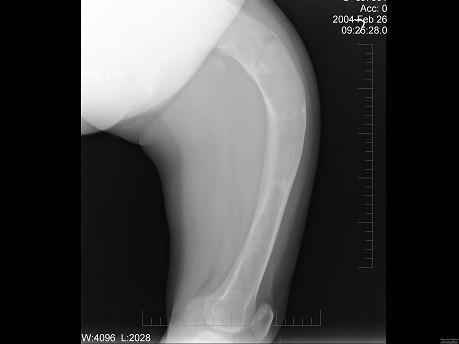

问题 男,17岁,下肢畸形,有皮肤色素沉着,性早熟等,结合图选出最佳答案 ( )

选项 A、内生软骨瘤 B、畸形性骨炎 C、骨巨细胞瘤 D、骨纤维结构不良 E、非骨化性纤维瘤

答案 D